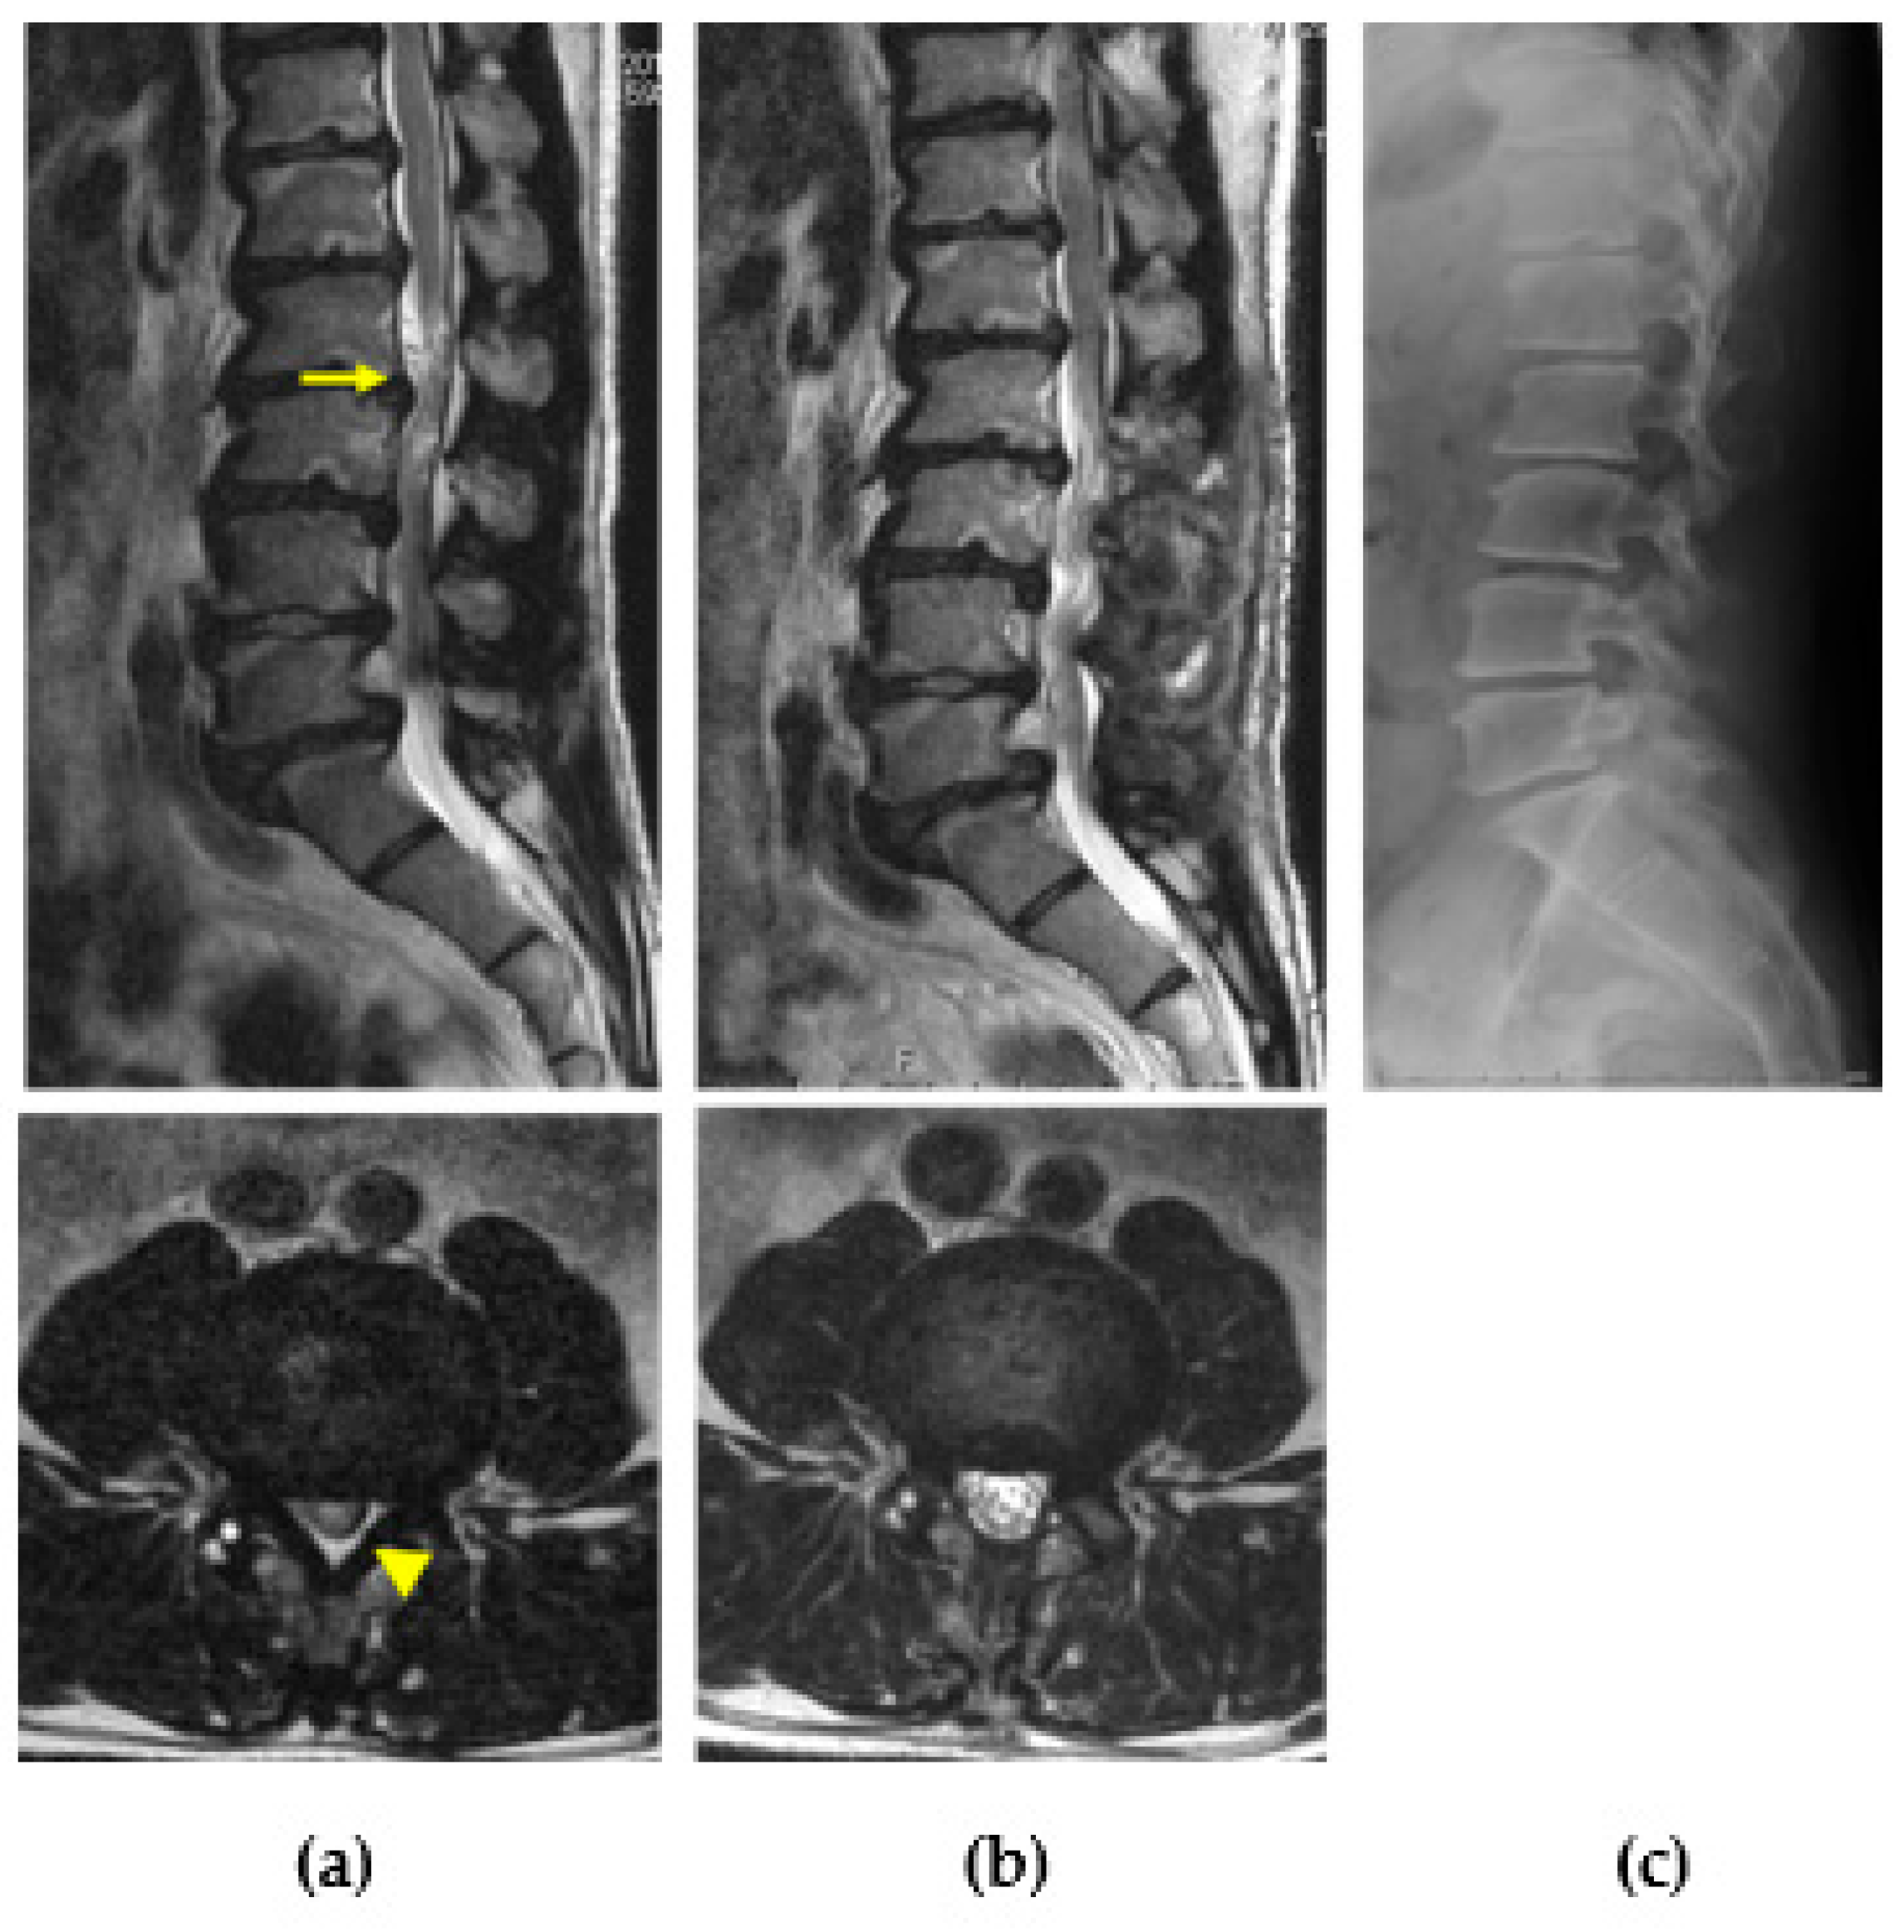

Figure 9.

Lumbar canal stenosis in MPS II. Preoperative magnetic resonance images of a 37-year-old man with MPS II showing lumbar canal stenosis with redundant nerves (arrow), multiple disc degeneration and bulged discs, and hypertrophied ligamentum flavum (arrowhead) (a). Intermittent claudication disappeared after posterior decompression surgery. The spinal canal was enlarged, and nerve root redundancy also disappeared in postoperative magnetic resonance images (b). Vertebral deformity was not evident compared with MPS IV; however, isthmic spondylolysis and degenerative changes were observed in the plain radiograph (c).